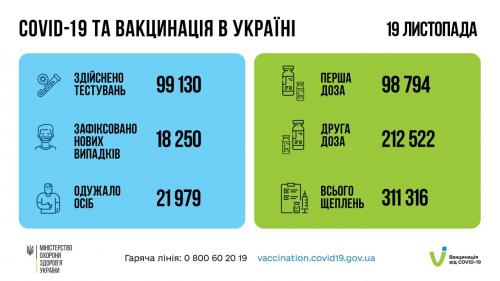

МОЗ: Уперше з початку пандемії було зроблено понад 100 тисяч ПЛР-досліджень за добу